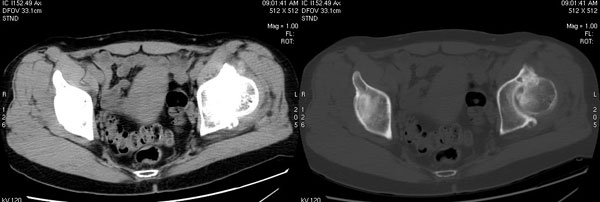

以下是引用jiajie在2006-7-14 17:19:00的发言:[br]ct所见:双侧髋关节不对称,左侧关节间隙变窄,关节面毛糙。左侧股骨头变形、无明显变小,前上缘与髋臼融合,融合处骨质明显增生硬化,并见数个小囊变影。股骨头下端与股骨颈交界部见囊样变,邻近肌肉内见囊样密度减低区,ct值24hu。右侧髋关节形态未见异常。[br][br]ct诊断:左侧髋关节结核可能,请结合临床资料进一步分析。

以下是引用lihuuuu在2006-12-5 10:14:00的发言:[br]定位像示:左侧髋臼变浅,倾斜度加大,髋臼外上缘呈波浪状不规则,骨质增生硬化,髋关节上缘间隙明显变窄,股骨头向外上轻度移位。轴位像示:左侧股骨头变形,前上缘与髋臼融合,融合处骨质明显增生硬化,并见数个小囊变影。股骨头下端与股骨颈交界部见囊样变,邻近肌肉内见密度减低区,ct值24hu,内缘见弧形高密度钙化影。右侧髋关节形态未见异常。[br]ct诊断:左侧髋臼发育不良[br] 左侧股骨头缺血性坏死[br] 左侧肌肉内低密度影伴有高密度钙化-考虑早期骨化性肌炎[br] [br]“我认为在描述上已经写了肌肉部分,印象诊断里应该写主见”[br]